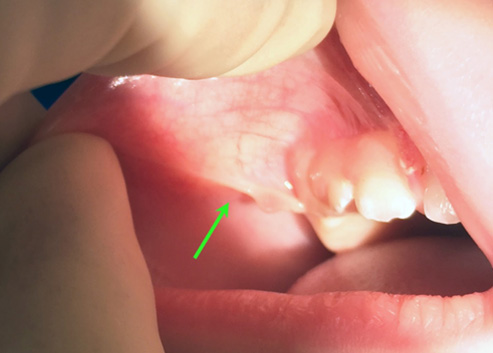

A tongue-tie (ankyloglossia) is a movement restriction of the tongue caused by an excessively tight thin tissue (frenum) connecting the tongue and the floor of the mouth. Equally, a lip-tie occurs when the tissue between the upper lip and the gums does not allow the lips to move freely, and a cheek-tie influences the movement and functioning of the cheeks.